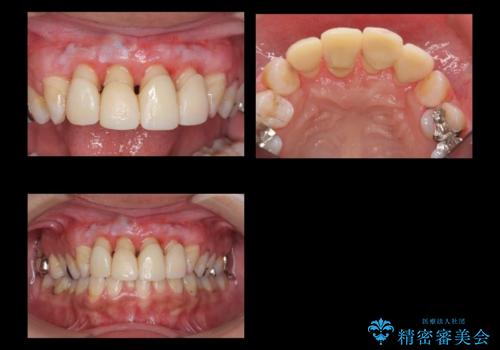

前歯の虫歯 つぎはぎの歯をセラミックに

隣の歯もつぎはぎでプラスチックが劣化していたため、虫歯を取りセラミックでかぶせました。

保険治療の前歯の被せものの縁(マージン)が歯茎の中まで及んでいたため、歯周外科手術を行い、マージンが歯肉縁下深くならないように設定しました。

- 63.8万円(右上4~左上2:emaxクラウン 7万円x6本、仮歯 1万円x6本、歯周外科手術 15万円、右上1:精密根管再治療 9万円およびファイバーコア2万円)費用は治療当時の料金となります